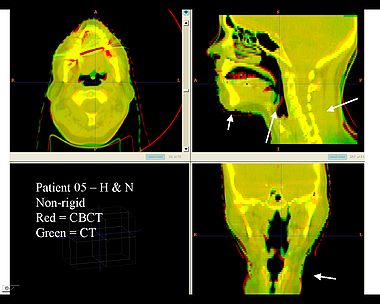

This first example shows the kind of anatomic changes that can occur in head and neck cancer. The pre-treatment scan is in green, and the mid-treatment scan is in red. The image on the left is the rigid registration, on the right is deformable registration.